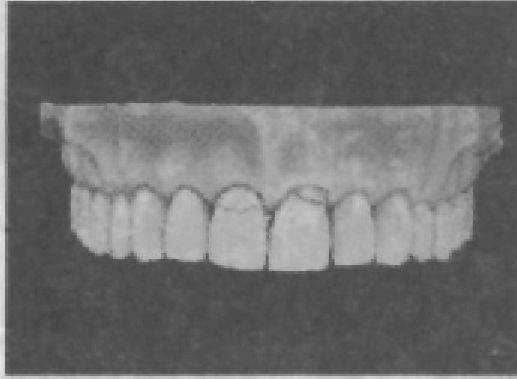

Зубные ряды при ортогнатическом прикусе располагаются по отношению к окклюзионной плоскости так: режущие края резцов, вершины клыков и дистальный щечный бугорок третьего

моляра касаются этой плоскости, первый и второй премоляры и моляры расположены ниже плоскости. Центральные резцы и клыки верхней челюсти на 2—3 мм ниже окклюзионной плоскости. Щечные бугорки премоляров и моляров также пересекают эту плоскость (рис. 22).

Такое расположение коронок зубов и их окклюзионных поверхностей обусловливает кривизну зубной дуги в переднезаднем (рис. 23) и боковом направлениях. Если провести линию по режущим краям передних зубов и щечным бугоркам (или фиссурам) жевательных зубов, то образуется сегмент окружности, обращенный выпуклостью книзу. Эта линия называется сагиттальной компенсационной кривой, или кривой Шпее. У зубного ряда верхней челюсти она начинается от первого премоляра. Разный уровень расположения щечных и небных бугорков вследствие наклона зубов в сторону щеки обусловливает наличие боковых (трансверсальных) окклюзионных кривых — кривых Уилсона — с различным радиусом кривизны у каждой симметричной пары зубов. Эта кривая отсутствует у первых премоляров (рис. 24).